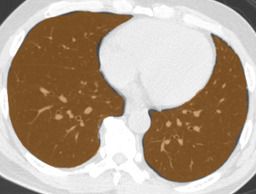

In this paper, we define partial annotation as an annotation format in which only one class is chosen for the annotation and only pixels belonging to the chosen class are annotated per image. For example, in Figure 1(a), although there is ground glass opacity in the image, only consolidation is chosen for annotation and pixels of consolidation are annotated. Partially annotated dataset is less informative for training, however, it is much easier to create compared to fully annotated dataset since annotators only need to focus on one class at a time during the annotation task.

Partially annotated datasets have been utilized previously [8, 9]. In this paper, we propose a new weak supervision technique that fully utilizes partially annotated dataset. Throughout this paper, each DLD pattern is represented or painted in the following colors (CON:cyan, GGO:yellow, HCM:red, EMP:green, NOR:brown.)

Statistics of our dataset are shown in Table 1 and typical images and their annotations for each DLD pattern are shown in Figure 1. In our partially annotated dataset, all the pixels in a slice were manually classified into two classes: dominating DLD pattern and other tissues. In other words, all the pixels in our dataset were assigned one of the labels from either of the two label sets, Lstrong={lCON,lGGO,lHCM,lEMP,lNOR}subscript𝐿𝑠𝑡𝑟𝑜𝑛𝑔subscript𝑙𝐶𝑂𝑁subscript𝑙𝐺𝐺𝑂subscript𝑙𝐻𝐶𝑀subscript𝑙𝐸𝑀𝑃subscript𝑙𝑁𝑂𝑅L_{strong}=\{l_{CON},l_{GGO},l_{HCM},l_{EMP},l_{NOR}\} or Lweak={lCON¯,lGGO¯,lHCM¯,lEMP¯,lNOR¯}subscript𝐿𝑤𝑒𝑎𝑘subscript𝑙¯𝐶𝑂𝑁subscript𝑙¯𝐺𝐺𝑂subscript𝑙¯𝐻𝐶𝑀subscript𝑙¯𝐸𝑀𝑃subscript𝑙¯𝑁𝑂𝑅L_{weak}=\{l_{\overline{CON}},l_{\overline{GGO}},l_{\overline{HCM}},l_{\overline{EMP}},l_{\overline{NOR}}\}. For example, in Figure 1(a), colored pixels were labeled as lCONsubscript𝑙𝐶𝑂𝑁l_{CON} and all the other pixels were labeled as lCON¯subscript𝑙¯𝐶𝑂𝑁l_{\overline{CON}}. In this paper, we call pixels of label lLweak𝑙subscript𝐿𝑤𝑒𝑎𝑘l\in L_{weak} and lLstrong𝑙subscript𝐿𝑠𝑡𝑟𝑜𝑛𝑔l\in L_{strong} as weakly annotated pixels and strongly annotated pixels respectively. Our pixel-wise annotations were created in the following steps. First, up to 3 slices were chosen for the annotation for each HRCT scan and for each slice, one representing DLD pattern was chosen by a radiologist. Second, three radiologists performed pixel-wise binary annotation (e.g. binary annotation between lCONsubscript𝑙𝐶𝑂𝑁l_{CON} or lCON¯subscript𝑙¯𝐶𝑂𝑁l_{\overline{CON}}) for each slice. Finally, the radiologists’ annotations were merged by taking majority classes for each pixel (i.e. pixels labeled as a DLD pattern by more than 2 radiologists became the corresponding DLD pixel). In addition to the DLDs annotation, lung fields were manually segmented under the supervision of radiologists and training and testing were conducted only within the lung fields.

Refer to caption

(a) CON \blacksquare

(b) GGO \blacksquare

(c) HCM \blacksquare

(d) EMP \blacksquare

(e) NOR \blacksquare

Figure 1: Typical slices for each DLD classes. Slices of HRCT are shown in lung window setting (window-center=-600, window-width=1500) with annotated labels superimposed in transparent colors. Note that even if more than one DLD patterns existed, only one DLD pattern was chosen and annotated for a slice to facilitate the annotation process.